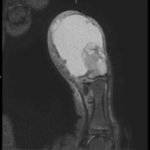

Magnetic resonance imaging (MRI) showed an “expansile, destructive solid and cystic mass with aggressive…characteristics…” (see images). Tissue biopsy confirmed a giant cell tumor arising from the bone. The patient underwent a debulking procedure, and later a distal amputation. Follow-up on pathology showed negative margins.

The best imaging study is MRI, to assess for bony and tissue involvement and surgical approach. Computed tomography may be used; however, it doesn’t delineate the soft tissue and bony connections as well. Standard oncology labs should be drawn as well, including: CBC with differential, LDH, uric acid, CMP, ESR. The growth of the tumor is insidious and therefore imaging should be done based on clinical concern. In the ED setting, if close follow up can be ensured, imaging can be done as an out-patient. Annual surveillance is recommended for at least five years in most patients, even after total resection, according to some studies.3